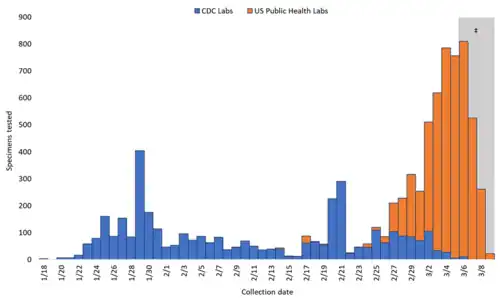

Nos Estados Unidos, os Centros de Controle e Prevenção de Doenças (CDC) desenvolveram o Painel de Diagnóstico por RT-PCR do Novo Coronavírus (2019-nCoV) que foi disponibilizado a laboratórios de saúde pública pela, International Reagent Resource, agência interna dos CDC.[8] Um dos três testes genéticos em versões mais antigas dos kits projetou resultados inconclusivos e um congestionamento em Atlanta; os testes, que utilizavam dois componentes, foram considerados fiáveis em 28 de fevereiro de 2020, permitindo que os laboratórios estaduais e locais finalizassem as análises de forma rápida. Seguidamente, o teste foi aprovado pela Food and Drug Administration sob uma autorização de uso de emergência.[9][10]

Os laboratórios comerciais dos Estados Unidos também começaram a realizar os testes. Em 5 de março de 2020, a LabCorp anunciou a disponibilidade nacional de testes de COVID-19 com base na RT-PCR.[11][12] A Quest Diagnostics disponibilizou, similarmente, o teste nacional de COVID-19 em 9 de março de 2020. Nenhuma limitação de quantidade de realização dos testes foi estipulada; a coleta e o processamento das amostras devem ser realizadas de acordo com os requisitos dos Centros de Controle de Doenças e Prevenção.[13]